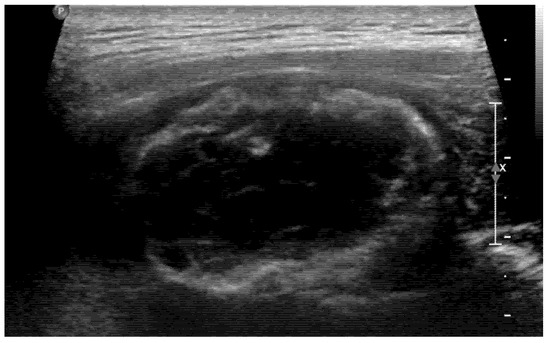

Usually, we do not perform a biopsy when MO is suspected. However, in this case, the patient’s symptoms worsened, and its location was unusual for MO, so both the clinician and patient strongly wanted to perform a biopsy. Therefore, to confirm the diagnosis and exclude the possibility of malignancy, we decided to perform a US-guided biopsy. In the US, hyperechoic peripheral rim calcification with posterior shadowing was noted (Figure 4). A US-guided needle biopsy was performed, and the pathological report confirmed myositis ossificans with zone phenomenon (Figure 5).

Figure 4. In the US, calcified peripheral rim and posterior shadowing were noted. A US-guided biopsy was performed.